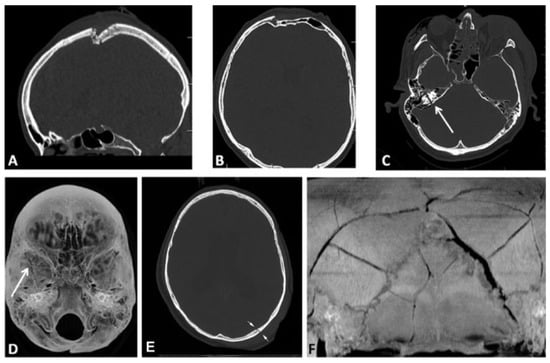

This coding system allows description of most relevant fracture patterns as illustrated in the case examples, such as the differentiation between unilateral or bilateral fracture patterns. In a series of three case examples, we illustrate the coding of a case with multiple cranial vault fractures (Figure 5), a single skull base fracture extending into the temporal cranial vault (Figure 6) and a right occipital and temporal cranial vault fracture extending into right middle fossa skull base (Figure 7). A range of additional fracture patterns are presented in a special case appendix as electronic supplement to this issue of the Journal (www.aocmf.org/classification).

Figure 5. Multiple cranial vault fractures. (A–F) Multiple cranial vault fractures. The right sided fractures involve the frontal and parietal vault with comminution and depression and extension inferiorly into the temporal cranial vault. Similarly, on the left, there is a linear parietal vault fracture that appears to continue into the temporal bone. (G) There is extension of these fractures into the left and right sphenoid bone. Imaging: Computed tomographic axial views. (H) Level 3 code: 93 S0.m.S0, 94 F1.P1.T0.m.T0.P0, This case example CMTR-93-94-001 is made available electronically for viewing using the AOCOIAC software at www.aocmf.org/classification.